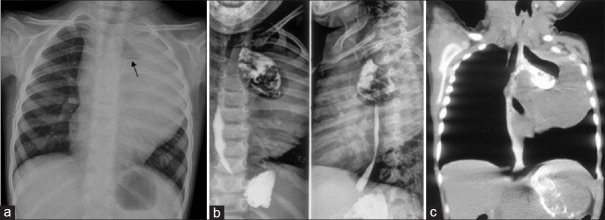

摘要:由食道引起的腹腔外类脂样纤维瘤病以及同时因食道肿瘤引起的牵引性憩室极为罕见。我们介绍了一名两岁女孩的这种复杂情况,这种情况给手术带来了挑战,需要同时处理多种病变。手术同时处理了两种病变,憩室的存在有助于实现阴性手术切缘。

Abstract: Extra-abdominal desmoid fibromatosis arising from the oesophagus and the contemporaneous traction diverticula due to an oesophageal tumour is extremely rare. We present this complex situation in a 2-year-old girl which posed a surgical challenge requiring simultaneous management of multiple pathologies. Surgery addressed both the entities and the presence of the diverticulum facilitated achieving negative surgical margins.